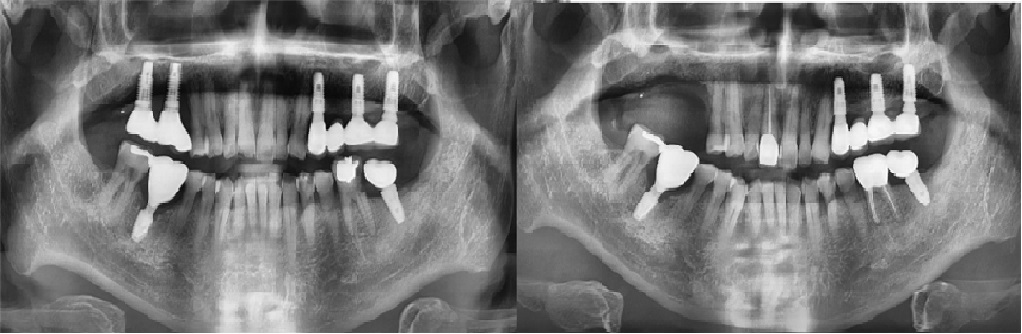

치료전후사진